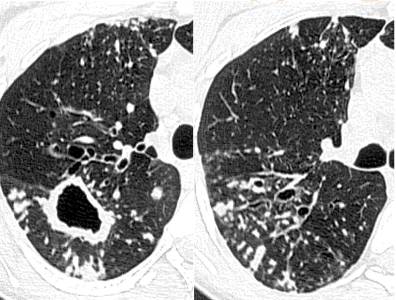

先天性囊性纤维化:高分辨率CT扫描显示支气管扩张、支气管壁增厚和弥散性树芽征

闭塞性细支气管炎:高分辨率CT表现包括中枢和外周支气管扩张,支气管壁增厚。呼气相高分辨率CT是闭塞性细支气管炎检出最敏感的方式。